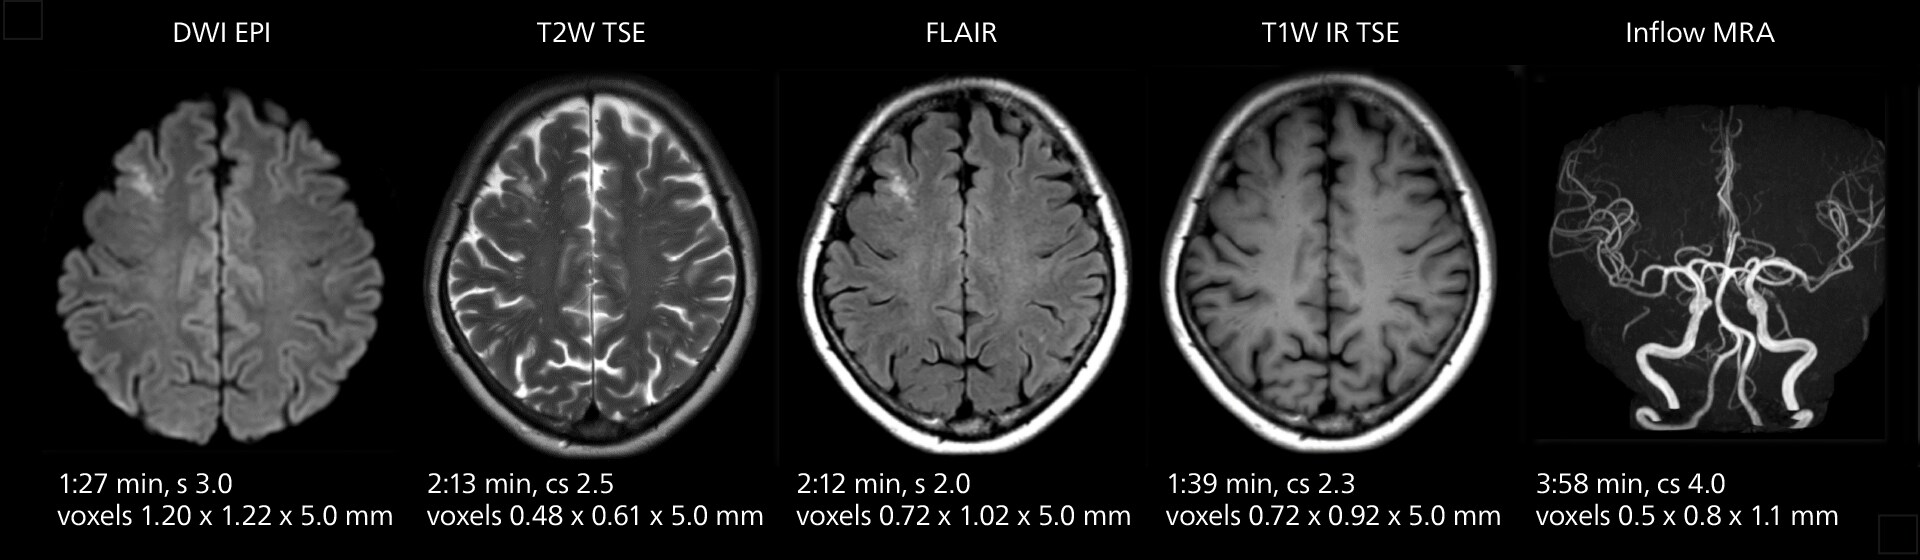

Clinical case example: Brain MRI

These images of an old cerebral infarction demonstrate the speed and image quality after upgrading to Elition X.

Brain MRI showing an old cerebral infarction